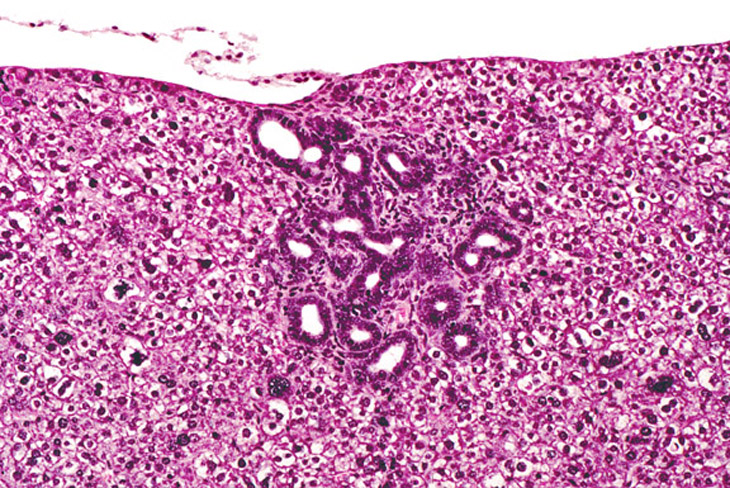

A transient ductular formation of hepatocytes is seen in liver of this 2-week old AL-TAg mouse.

Bile duct proliferation in a 4-week old AL-TAg mouse. Some surrounding hepatocytes are dysplastic